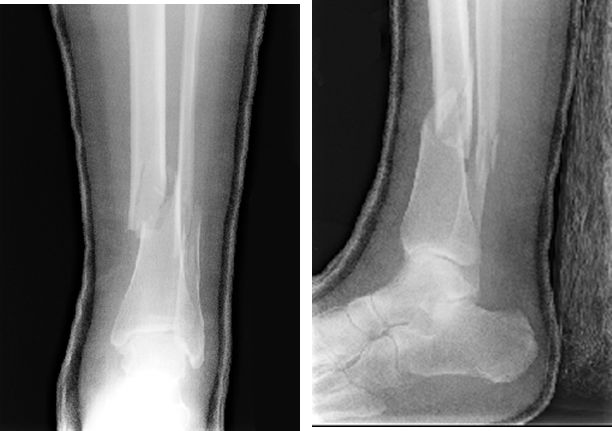

Maisonneuve Fracture

腓骨中段骨折

下胫腓分离